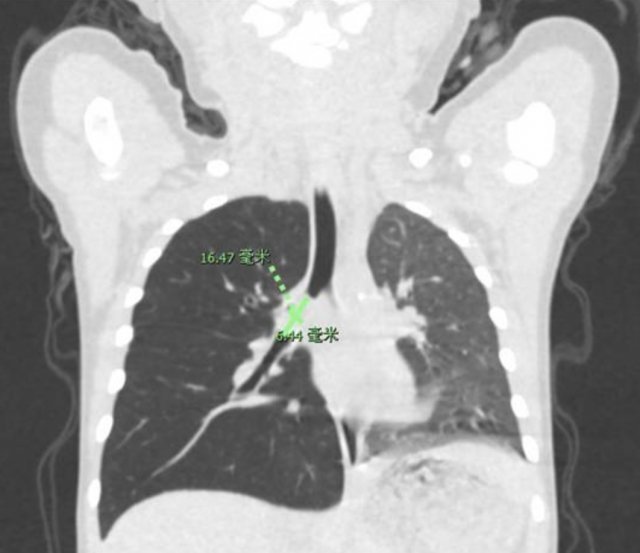

▲從 CT 圖片可以看出,欣欣右側(cè)肺部因?yàn)楫愇锒氯€引起了阻塞性肺氣腫。

在那之后欣欣一直有間斷性咳嗽,并有喘鳴。家長(zhǎng)不放心,便帶欣欣到深圳市兒童醫(yī)院,通過(guò)胸部 CT 發(fā)現(xiàn),欣欣的右主支氣管有異物。了解到孩子的病因之后,醫(yī)護(hù)人員馬上為欣欣完善術(shù)前準(zhǔn)備,耳鼻咽喉科醫(yī)師及麻醉科手術(shù)室醫(yī)護(hù)團(tuán)隊(duì)進(jìn)行了全麻手術(shù),欣欣氣管內(nèi)的異物——開(kāi)心果被順利取出。